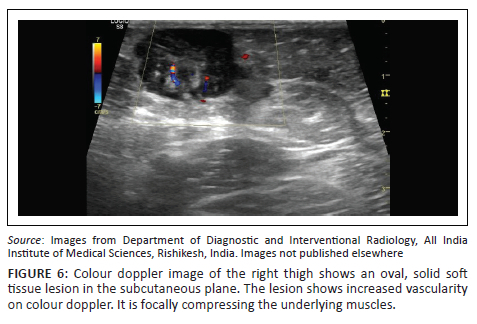

Focused ultrasound of the right thigh swelling revealed a hypoechoic soft tissue lesion in the subcutaneous plane with mild to moderate internal vascularity on colour doppler (Figure 6). Abdominal ultrasound examination showed multiple sub-centimetre retroperitoneal and mesenteric lymph nodes.

Subcutaneous involvement is known and was seen in this case as a subcutaneous thigh lesion. Thoracic involvement has been reported in a few cases. These cases included RDD presenting as a lung mass in one report and epicardial involvement in another case.1,13